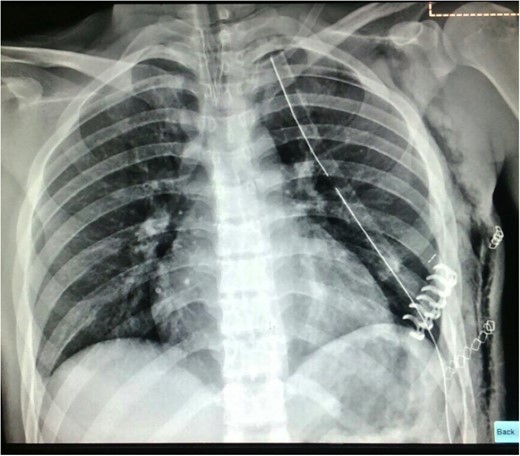

The chest CT showed moderate hemothorax, pneumothorax, a displaced fracture of the fifth left rib, and protrusion of a lung segment through a chest wall defect (Fig. 1).

A chest tube was inserted through the fourth left intercostal space (ICS) and connected to a water seal device (Aquaseal TM) on −20 cm H2O suction.

A longitudinal incision was made over the fractured rib (Fig. 4). A displaced rib fracture was observed. Bone segments were reduced and fixed using a 6 cm titanium plate (STRATOSTM System). A chest tube was inserted through the seventh ICS and connected to a closed water seal device on suction (Fig. 5).